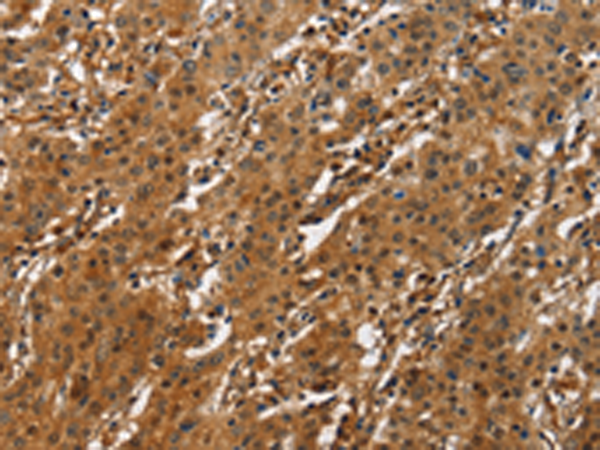

分类: 科研抗体货号: P07124别名: CREB2; TXREB; CREB-2; TAXREB67应用: IHC反应种属: Human, Mouse, Rat